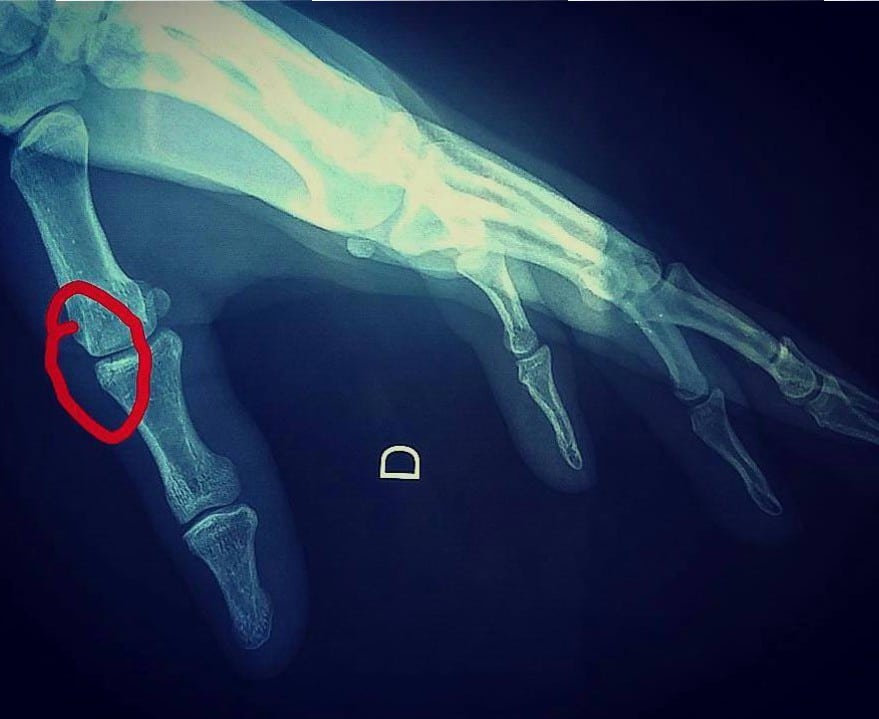

Tandis que ses fans croisaient les doigts dans l’espoir qu’il revienne au plus vite sur les podiums de la Coupe du monde, Benoît lui s’en cassait un (le pouce droit) à l’entraînement… Le pilote officiel Scorpa est donc privé de manche andorrane ; nous lui souhaitons d’être très rapidement de retour au top…